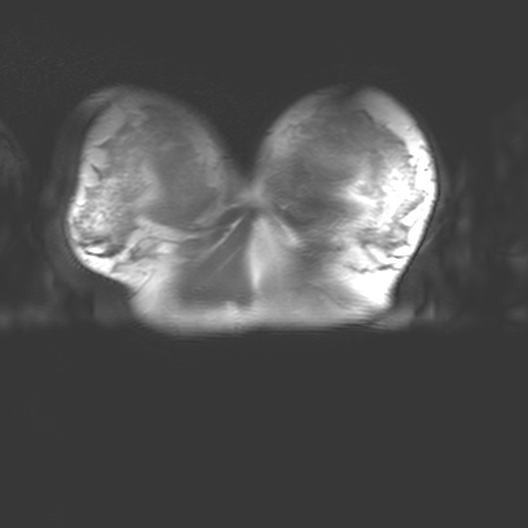

Corporeal matter as perceived by MRI straddles definitions of substance, organism, subject and object. MRI interacts with the body through nuclear magnetic resonance and electrodynamics, bringing us into contact with the body as a person, as an assemblage of biochemical reactions, as a patient and a cellular, molecular, atomic and subatomically composed entity.

MRI is a non-invasive biomedical imaging technology that visualises tissues within the body. MRI is an interesting piece of physics that interacts with the body. As a technology it draws on the quantume mechanical properties embedded in corporeal matter - particularly hydrogen ions, also known as protons (H+). MRI brings together multiple aspects of our ontology. MRI interacts with the body through nuclear magnetic resonance and classical electrodynamics and thus physics allows us to connect to the abject. This brings us into contact with the body as a person, a patient, a member of a community, and as a cellular, molecular, atomic and subatomically composed entity.

I began my investigation by taking part in MRI trials at the Cancer Centre in 2018 with Dr Heather Fitzke. MRI images confront us with the fact that our bodily materiality acts beyond us and that medical technology shapes our sense of self.

Seeing my organs autonomously pulsing on the monitor in the control room had a pronounced impact on me. It was like looking into a rockpool within my own body. The affecting power of MRI (its power to change our emotions) is in its potential to reveal autonomic bodily functions and diseases which are beyond our control. The data on the screen revealed my autonomous self: peristalsis, bowel movements, digestion, heartbeats and respiration. Through MRI, anatomy is seen as embedded and relational.

I felt a deep sense of fascination with how my organs moved and worked. Haraway’s situated biopolitics argues for an account of the body as an environment, in a state of simultaneous dissolution and formation which I notice in my data. My organs seemed like invertebrates in a rockpool: a squishy pulsing ecosystem. Organs do not operate in isolation but are interconnected. Their autonomous pulsing and motion seemed creaturely and strange in contrast to my numerous encounters with preserved cadavers in the dissecting room. My organs keep me alive yet I have no conscious sense of their functioning. They function beyond me.